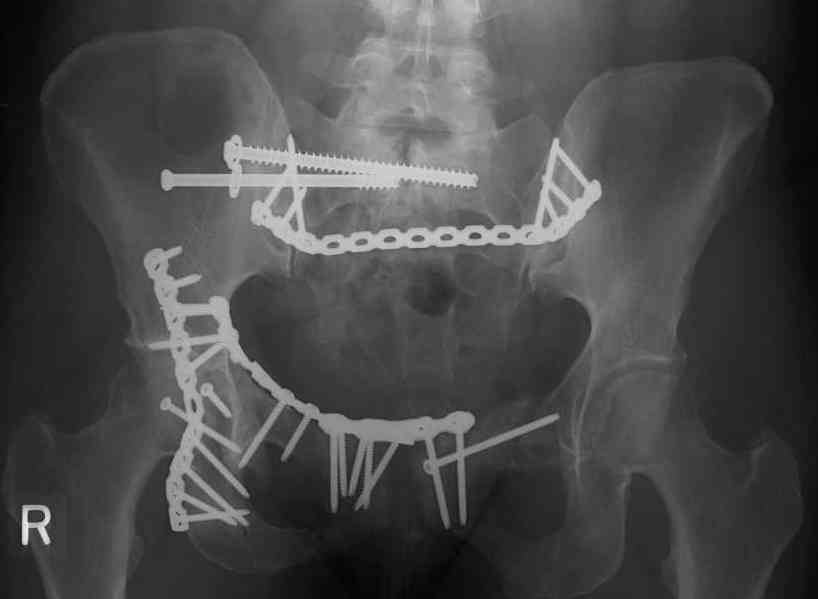

This is a 48 yo non-smoking female s/p MCC 10 months ago. I do not have the initial injury films. She underwent ORIF as shown on attached file.

She is having continued pain in low back/sacral region. Worse with sitting and prolonged walking. Has had pain since surgery. All of her wounds have healed uneventfully. Also has right hip pain laterally. No groin pain. Not aggravated with ROM of the hip. Infection work-up has been negative.

Any thoughts on the broken plate on the pelvic brim and the non-union on the anterior column. Doesn't seem like she's have pain from there.

Suggestions on treatment of sacral nonunion.